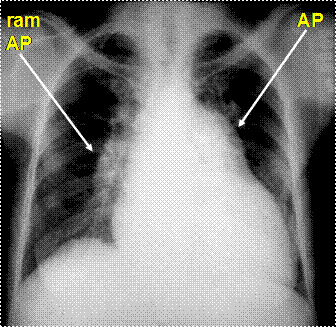

Rx cord-pulmon: circulatie pulmonara 'incarcata' cu ramurile AP dilatate in hiluri si extremitati 'retezate' avind periferie mult mai clara decat normal, bombare a conului arterei pulmonare, semne de hipertrofie VD

Imagine radiologica de HTP primara

Imagine radiologica de HTPS (DVPA) Imagine radiologica de HTPS (stenoza mitrala)

HTP secundara incipienta (DSA) HTPS severa (DSA Eisenmengerizat)

Imagine Rx. de profil cu HVD Aspect CT de HTP primara